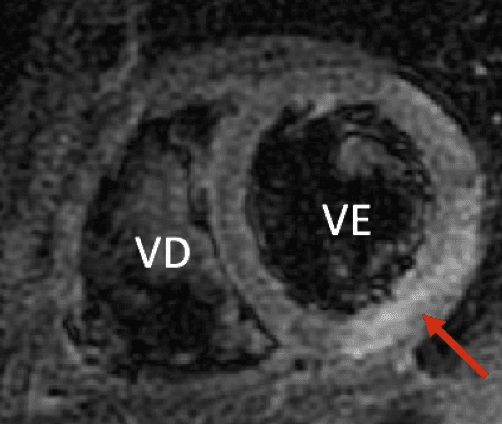

O que vemos nessa imagem???↓↓↓↓↓↓Resposta:O aneurisma do seio de Valsava é uma condição rara, que geralmente só causa sintomas após sua ruptura. É ocasionado pela separação ou pela falta de fusão e…